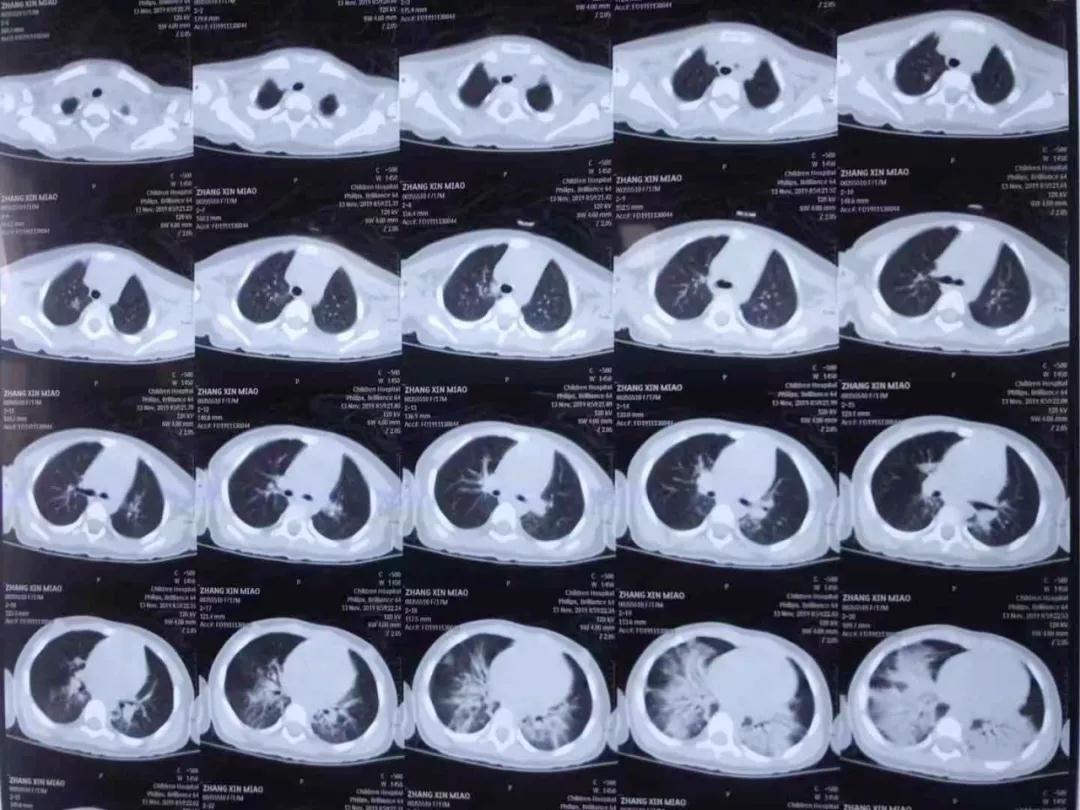

啪啪网 PICU主任单立业说,苗苗来院时呼吸困难、意识淡薄直接进入重症监护室,经检查是洗衣有机溶剂中毒,造成急性肺水肿、急性肺损伤以及心肌损害,随即给予无创呼吸机通气,抗炎、保护脏器功能等综合治疗。

5天120个小时,专家协同会诊、抢救、稳定患儿生命体征直至脱离生命危险,在重症监护病房治疗一周后,苗苗身体各项指标好转,撤掉呼吸机,转到普通病房,11月26日早上,苗苗出院回家。